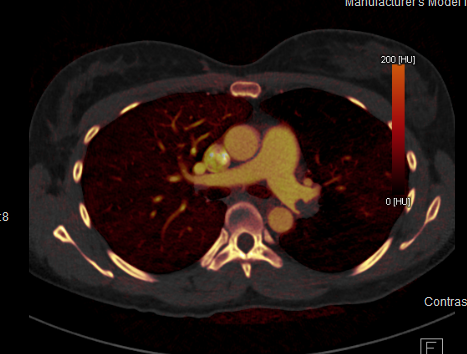

At M&D Radiology, we’re dedicated to achieving imaging excellence using state-of-the-art Siemens equipment, ensuring a distinctive patient experience with precise and rapid pathology diagnosis, all within the stunning surroundings of Johannesburg Surgical Hospital in Northcliff.

Our founding aspiration was to create a radiology practice distinguished by its utilisation of cutting-edge equipment for imaging and interventional procedures. Our primary objective was to harness the power of advanced technology to deliver the highest-quality imaging data, thereby empowering referring physicians to provide optimal treatment for their patients.